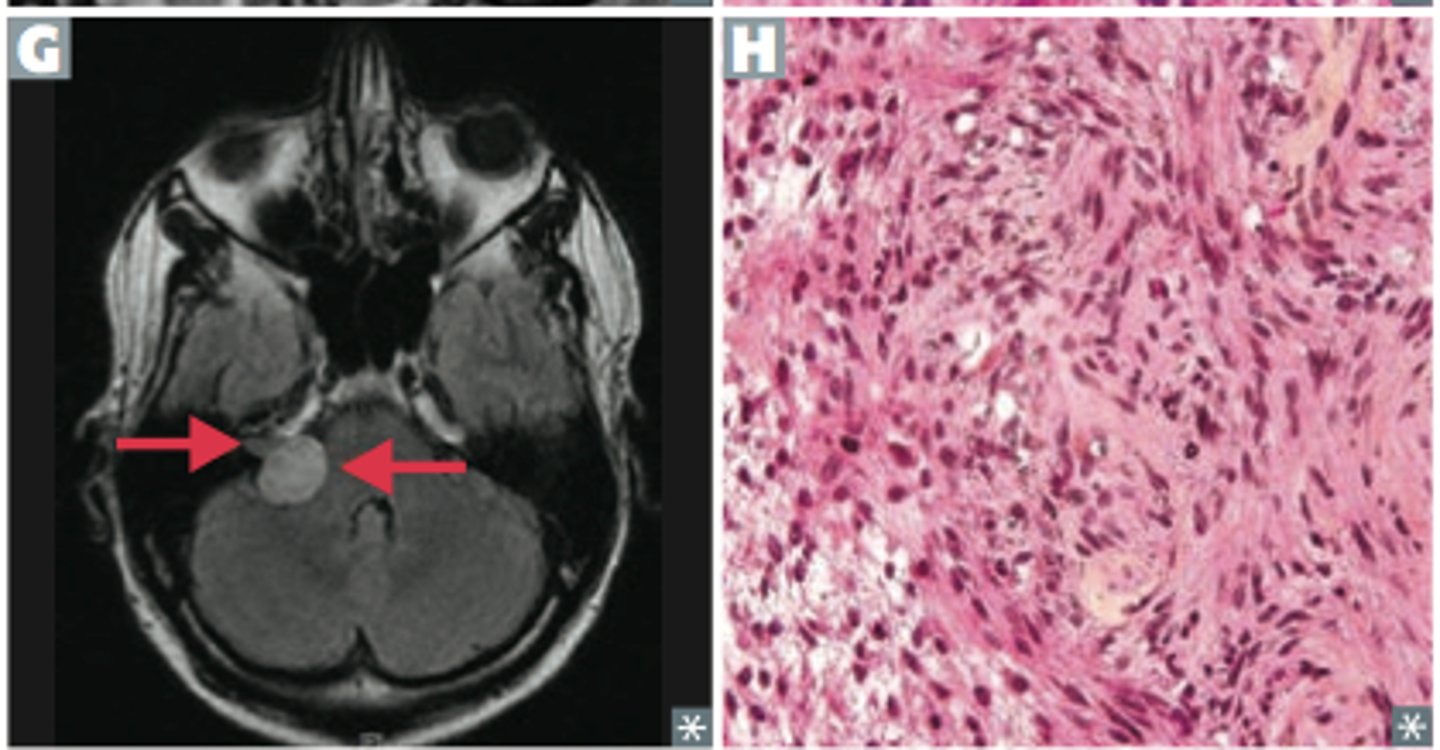

Bilateral acoustic schwannomas

Neurofibromatosis type 2

occur in cerebellopontine angle, S100 marker

Bilateral hilar adenopathy, uveitis, high ACE, hypercalcemia (activated macrophages for Vit D), interstitial fibrosis, erythema nodosum, high CD4

Sarcoidosis (non-caseating granulomas)